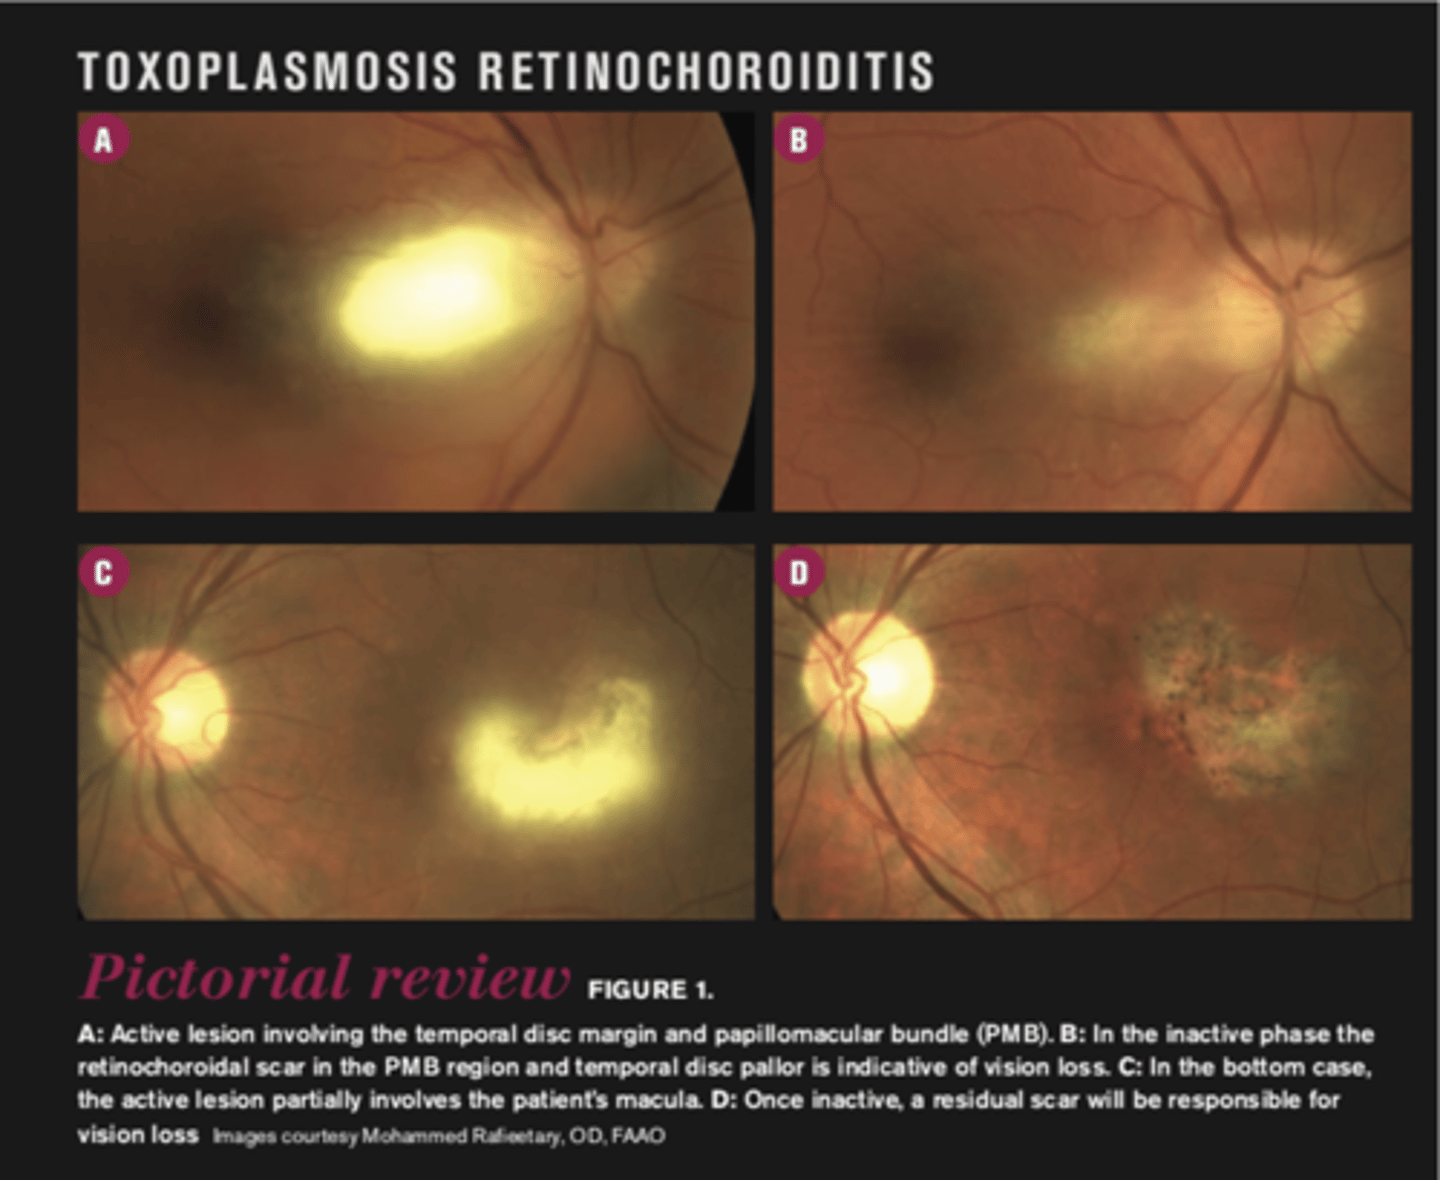

What is ocular toxoplasmosis?

focal, full-thickness retinochoroiditis

What are the 3 main ocular findings of ocular toxoplasmosis? Differentiate which are active vs latent.

white focal retinitis = active only

overlying vitritis = "headlight in the fog" = active only

nearby large pigmented retinochoroidal scar = active and latent

What is the prognosis for ocular toxoplasmosis?

4-6 weeks until lesion resolves

macular scarring = vision loss

risk of recurrence is high within 1st year of initial episode (esp at edge of initial scar where Bruch's is compromised)

What finding of toxoplasmosis is seen in A/B?

retinitis turns into hazy scar with nerve pallor

What finding of toxoplasmosis is seen in C/D?

scarring overtime with VA loss/scotoma